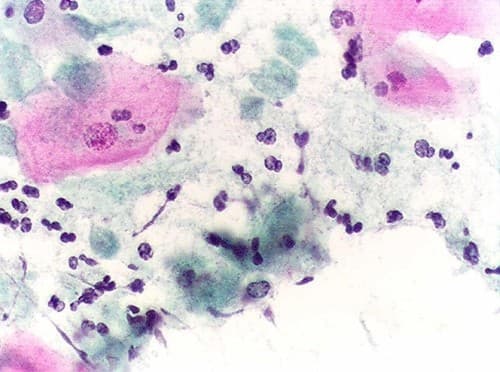

Nấm phụ khoa là căn bệnh nhiều chị em mắc phải. Nhưng những kiến thức liên quan đến căn bệnh này không phải chị em nào cũng nắm rõ. 1. Nấm phụ khoa là gì? Nấm phụ khoa là bệnh do rất nhiều loại nấm Candida khác nhau gây ra, nhưng phổ biến và điển […]

Nhiễm nấm Candida khiến người bệnh không khỏi lo lắng. Vậy căn bệnh này có ảnh hưởng đến sức khỏe như thế nào? 1. Nấm phụ khoa Candida là gì? Bệnh nhiễm nấm Candida là một bệnh nhiễm trùng do nấm Candida, thường gặp là nấm Candida albicans gây ra. Loại nấm này có có […]